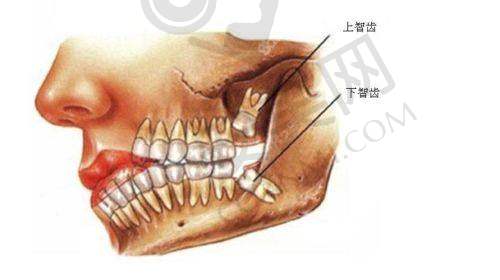

玉溪舒尔口腔医院的智齿拔除价格分为不同阶段。380元起的价格是基础价位,针对的是一些比较容易拔除的智齿,比如已经完全萌出,位置比较正,拔除难度相对较低的智齿。对于这类智齿,医生操作相对简单,所需时间也较短。而对于一些位置比较特殊的智齿,价格则会相应提高。例如,部分埋伏在牙龈下的智齿,需要先切开牙龈,去除部分牙槽骨才能拔除,这种情况下价格可能在800 - 1500元左右。还有一些完全埋伏在颌骨内的智齿,拔除难度更大,手术过程更复杂,价格可能会超过1500元。需要强调的是,以上价格仅供参考,实际价格会根据智齿的具体情况和患者的个体差异有所不同。